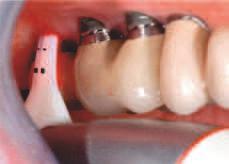

Implantur le pter go d ene au fost def n te ca f nd „[un] mplant plasat pr n tuberoz tatea max lară în placa pter go dă” (f g. 4). Implantur le pter go d ene traversează tuberoz tatea max lară d n reg un le molarulu secund sau terț edentat pentru a se ancora în osul cort cal dens format de peretele poster or al tuberoz tăț max lare, procesul or zontal al osulu palat n ș procesul pter go d al osulu sfeno d.

Aceste mplantur au, de ob ce , un d ametru între 3,5 mm ș 4,3 mm ș o lung me cupr nsă între 18 mm ș 25 mm, cu angulaț ale bontur lor mult -un t de până la 60 grade. Astfel de lung m sunt necesare pentru a as gura că vârful mplantulu se ancorează în osul cort cal al sutur pter gopalat ne după ce traversează țesutul gros adesea prezent în tuberoz tatea max lară. Angulaț a dep nde ș de ungh ul peretelu poster or al s nusulu max lar ș de prox m tatea acestu a față de peretele poster or al tuberoz tăț maxlare. Implantur le pter go d ene au adesea vârfur agres ve în formă de V, ascuț te ș auto-f letante pentru a as gura o ancorare stab lă la mplan-

tare ș colete cu f lete larg pentru a compr ma osul de dens tate scăzută d n reg unea tuberoz tăț max lare.